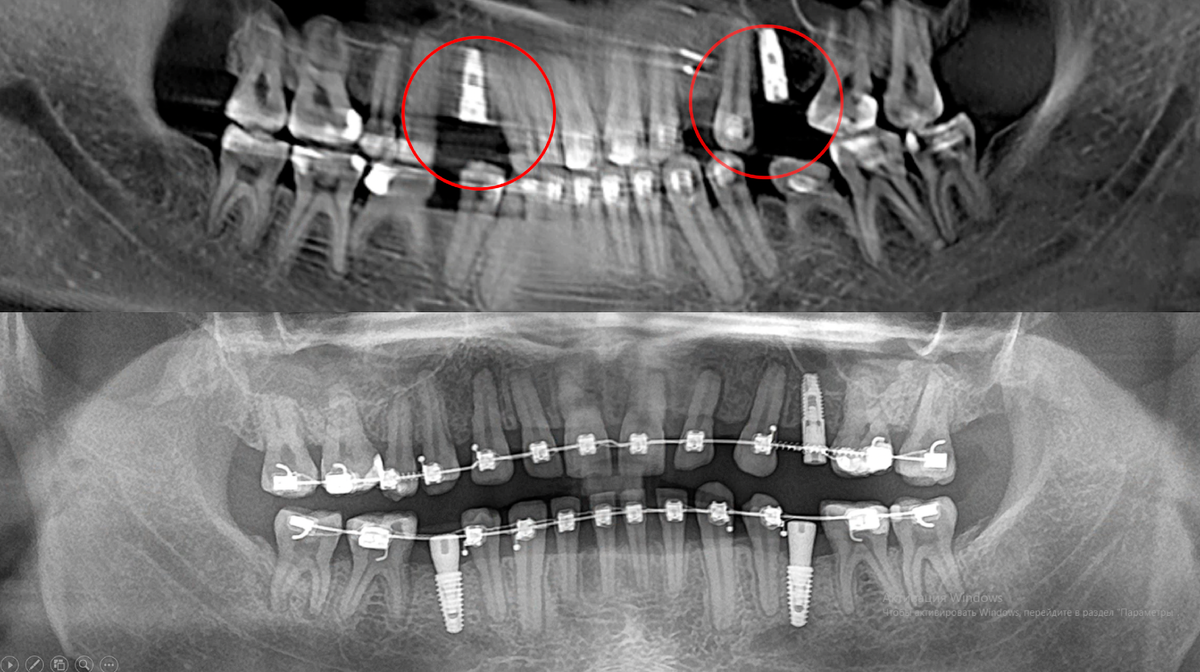

Перед нами пациент с очень сложной судьбой лечения. Он уже 9 лет проходит ортодонтическое лечение на брекетах. Мы — третьи ортодонты и уже третья клиника.

В чем проблема? С одной стороны у пациента всего два премоляра, но при этом было создано место еще для двух дополнительных премоляров. Клык зачем‑то сместили в сторону, появилось пространство, то ли под третий резец, то ли под второй клык. А в другом участке, наоборот, место уменьшили и установили имплантат.

Создается ощущение полного сюрреализма — как будто Алиса в Стране чудес. Много лишнего пространства, непонятная логика перемещений зубов и имплантаты, установленные просто «чтобы закрыть дырку».

В результате один из имплантатов пришлось удалить. Мы заново, грамотно распределили зубы, создали правильное пространство и установили два новых имплантата. Причем это сделал тот же хирург, который ставил предыдущие имплантаты. Именно он в итоге и спас пациента от последствий неправильного ортодонтического и ортопедического подхода, передав его нам.

Основная проблема этого случая — полное отсутствие планирования. Зубы двигали хаотично, создавали непонятные промежутки, а имплантаты устанавливали без учета будущего протезирования.

Важно понимать: имплантаты блокируют перемещение зубов. После их установки ортодонт уже не может сместить зубы в правильное положение.

В итоге пациент потерял 6 лет жизни, огромное количество времени, денег и сил. Часть имплантатов пришлось удалить, часть — переустановить заново.